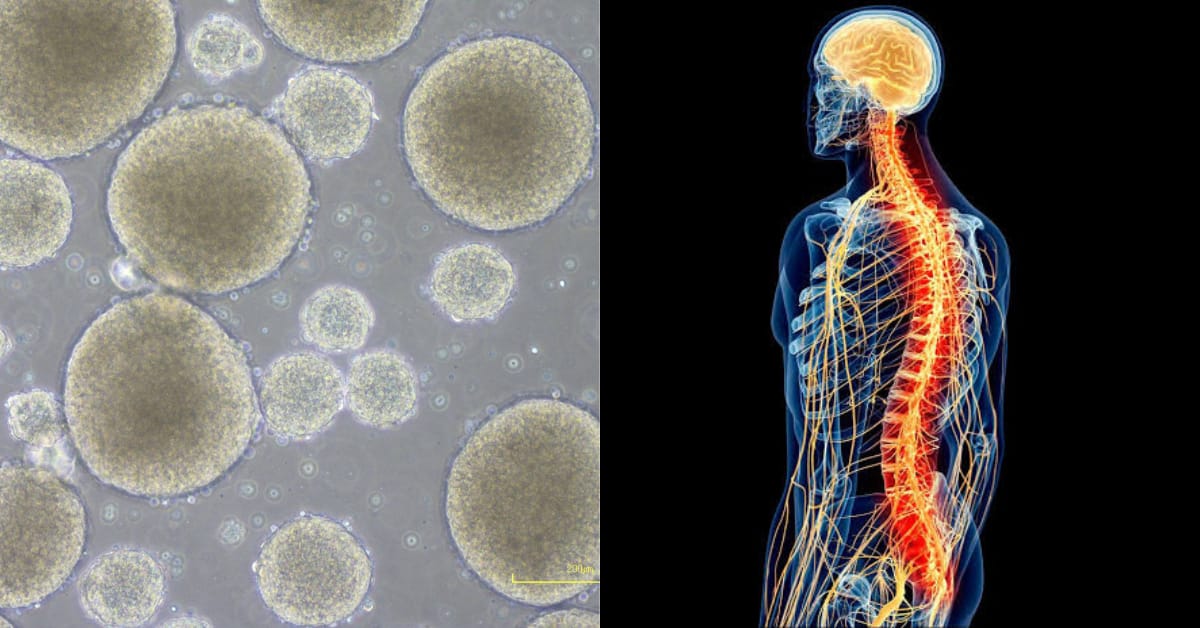

El equipo de científicos de la Universidad Keio en Tokio, se encuentra realizando estudios diversos que involucran células madre pluripotentes inducidas (iPS), con el objetivo de desarrollar metodologías para que sean utilizadas en el tratamiento de lesiones diversas.

El grupo de cirujanos de la Universidad Keio de Tokio, tiene como objetivo el estudio de células madre pluripotentes inducidas (iPS), para comprender e investigar con certeza si es posible el que puedan ser utilizadas en el tratamiento de lesiones.

Las creación de células iPS se lleva a cabo mediante la estimulación de células maduras, ya especializadas, regresándolas a un estado juvenil.

Posteriormente se les puede inducir para que maduren en diversos tipos de células, indica el estudio de la Universidad de Keio en el que utiliza células derivadas de iPS del tallo neural.

La primera fase del ensayo consistió en la implantación de más de 2 millones de células derivadas de iPS en la médula espinal de un paciente, mediante una cirugía llevada a cabo el mes pasado.